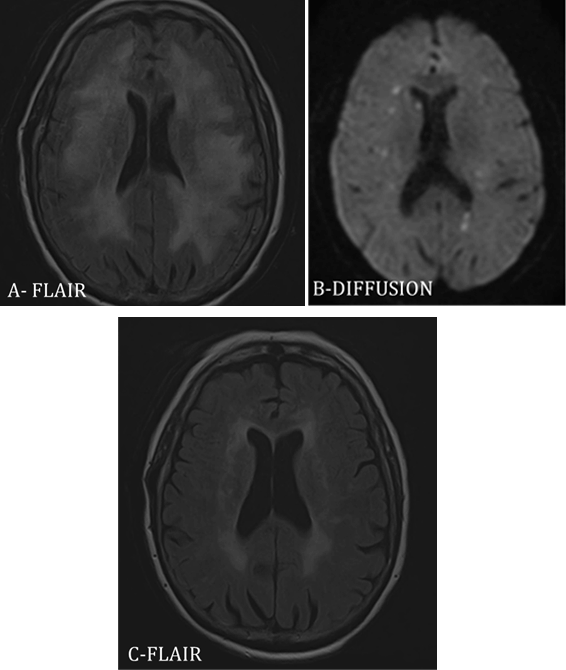

Usual blood analyses and explorations of hypothalamo-pituitary axis were normal. Lumbar punctures revealed an inflammatory fluid with predominantly lymphocytic cells (141 cells/mm3), increased protein level (1 g/L) and normal sugar level but no malignant cells. Anti-neuronal antibodies were absent. No infections agent was found in the CSF. Brain MRI scan revealed leukoencephalopathy (Figure 1A), multiple multifocal recent ischemic defects (Figure 1B), with small-caliber arteries enhancing after injection, suggesting vasculitis of the small vessels. Electroencephalograms showed specific diffuse brain suffering. Medullary MRI scan was normal. Meningoencephalitis induced by IPI was suspected and the infusions were withheld.

A course of high-dose intravenous methylprednisolone was started, 1 g daily for five days then switched for 1 mg/kg oral prednisone, with slow dose tapering, with significant improvement in both motor and vigilance symptoms. However, walking instability and memory disorders worsened. Neurological examination two months later showed a partial improvement of all symptoms except for her urinary incontinence. The lumbar punctures revealed a persistent inflammatory fluid. Brain MRI scan showed a significant decrease of T2 hypersignals (Figure 1C), and only few recent ischemic defects. Six months after the last IPI infusion, the tumoral assessment was consistent with stable disease.

Figure 1: Brain MRI scan of the Case 3: (A) FLAIR imaging after three IPI infusions revealed periventricular hypersignal of leukoencephalopathy. (B) Diffusion imaging after three IPI infusions showed multifocal hypersignal corresponding to recent ischemic defects. (C) FLAIR imaging two months after high-dose intravenous methylprednisolone revealed a significant improvement with decrease of periventricular T2 hypersignal.